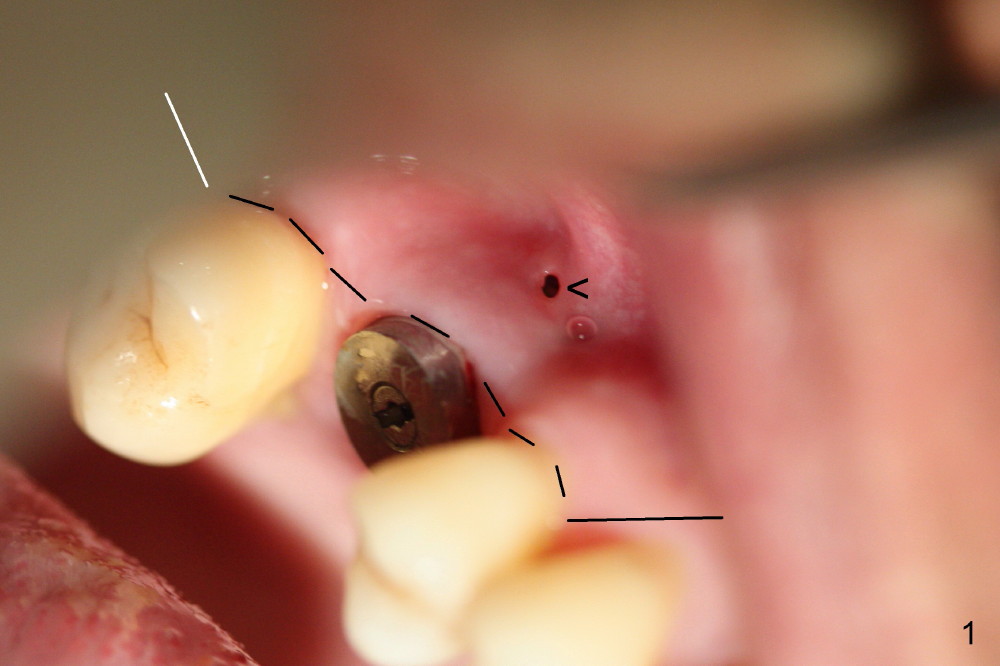

A fistula forms 3 months postop, buccal to the implant at the site of #3 (Fig.1 <). There are 2 possible reasons. First the implant was placed too buccally due to palatal root exposure before extraction. Second, the patient could not tolerate oral Amoxicillin. It is most likely that the buccal implant threads are not covered by the bone. Bone graft is required.

First, Clindamycin should be taken with Chlorhexidine mouth rinse 2 days prior to surgery. After incision (dashed line in Fig.1), the exposed threads are thoroughly irrigated, soaked with Clindamycin guaze 3 times, and treated with Perfogel and Endogain. Following allograft/Osteoten placement, Osteotape is used to cover the graft. Osteotape is a special collagen membrane with Osteogen already incorporated.